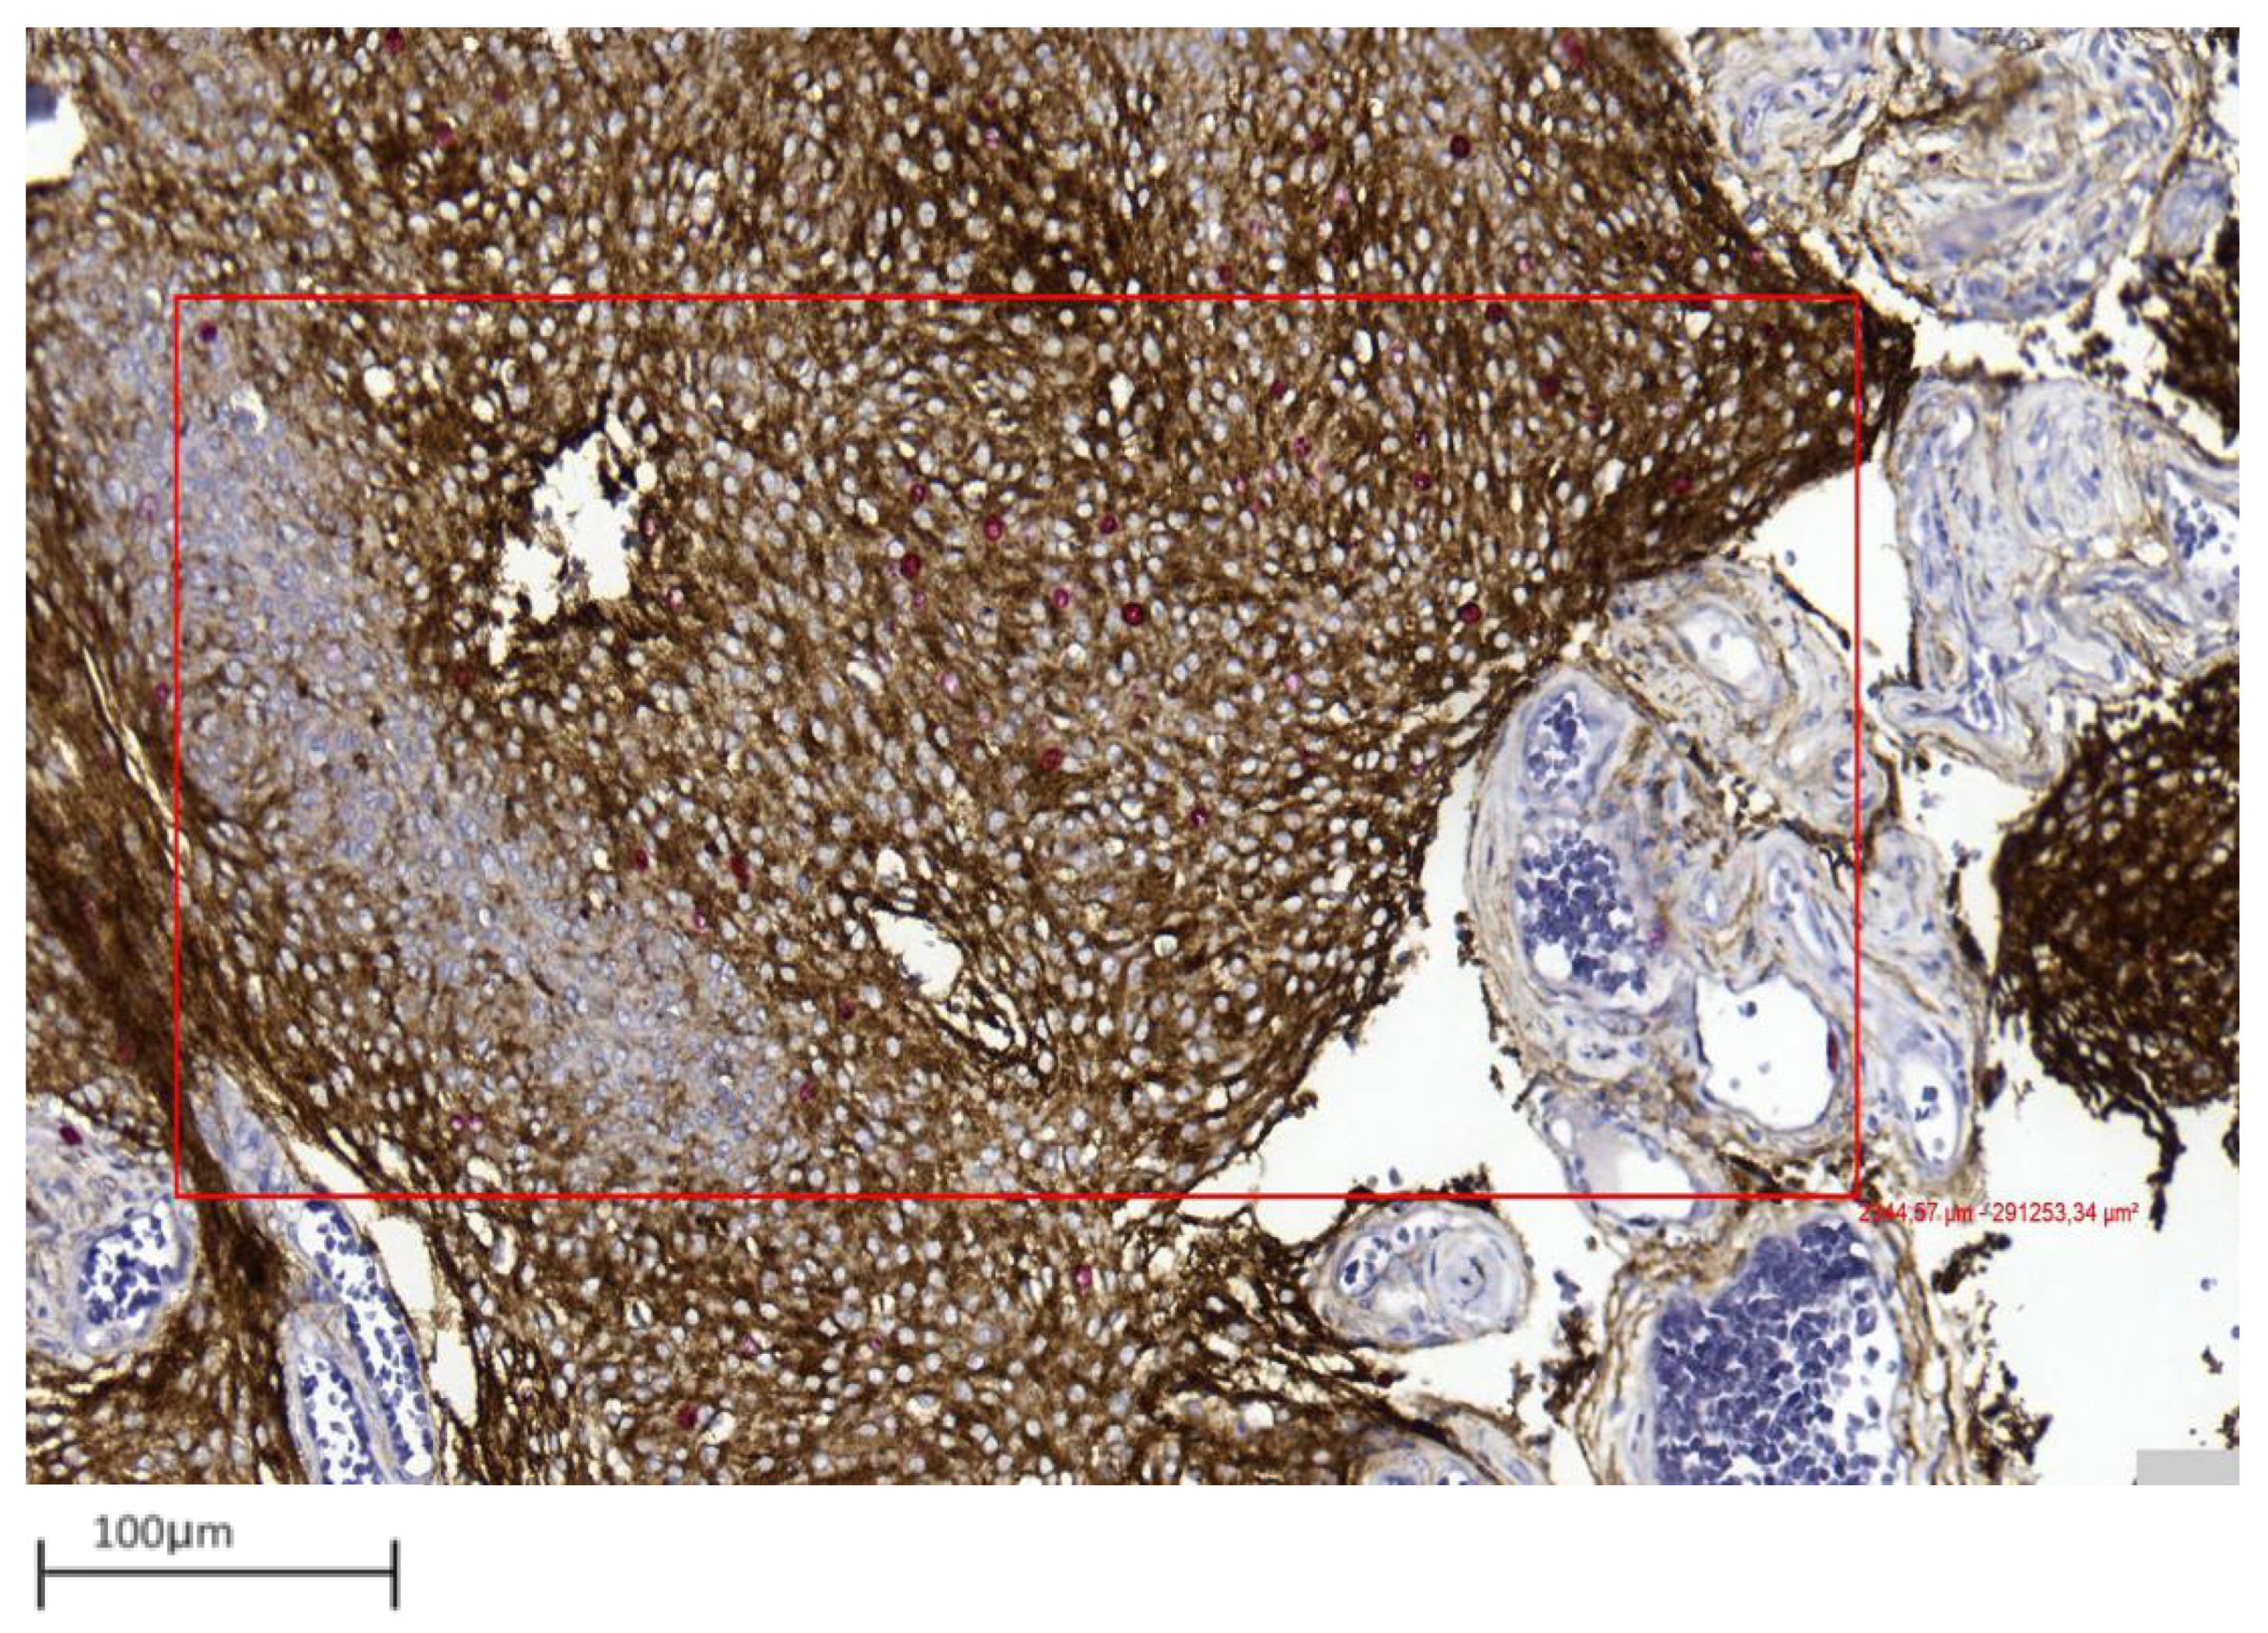

- Improved discrimination of neoplastic versus non-neoplastic cells: Unlike single-slice Ki-67 immunostaining (Figure 1), dIHC detects both markers on the same section, allowing precise differentiation between proliferating meningothelial tumour cells and components of the non-neoplastic microenvironment. EMA highlights the cytoplasm of meningothelial cells in brown, while Ki-67 marks proliferating nuclei in red. Only double-positive (EMA+/Ki-67+) cells are included in the PI count (Figure 2), whereas Ki-67-positive but EMA-negative elements (e.g., macrophages, lymphocytes, endothelial cells) are excluded (Figure 3).

Figure 2. Example of double immunohistochemistry (dIHC) in a grade 1 meningioma (case 7). Meningothelial cells show brown membrane staining, while Ki-67 is visualized in red (40× magnification).

Figure 4. Representative image showing area selection performed with a digital tool in a grade 1 meningioma (case 17) (10× magnification).